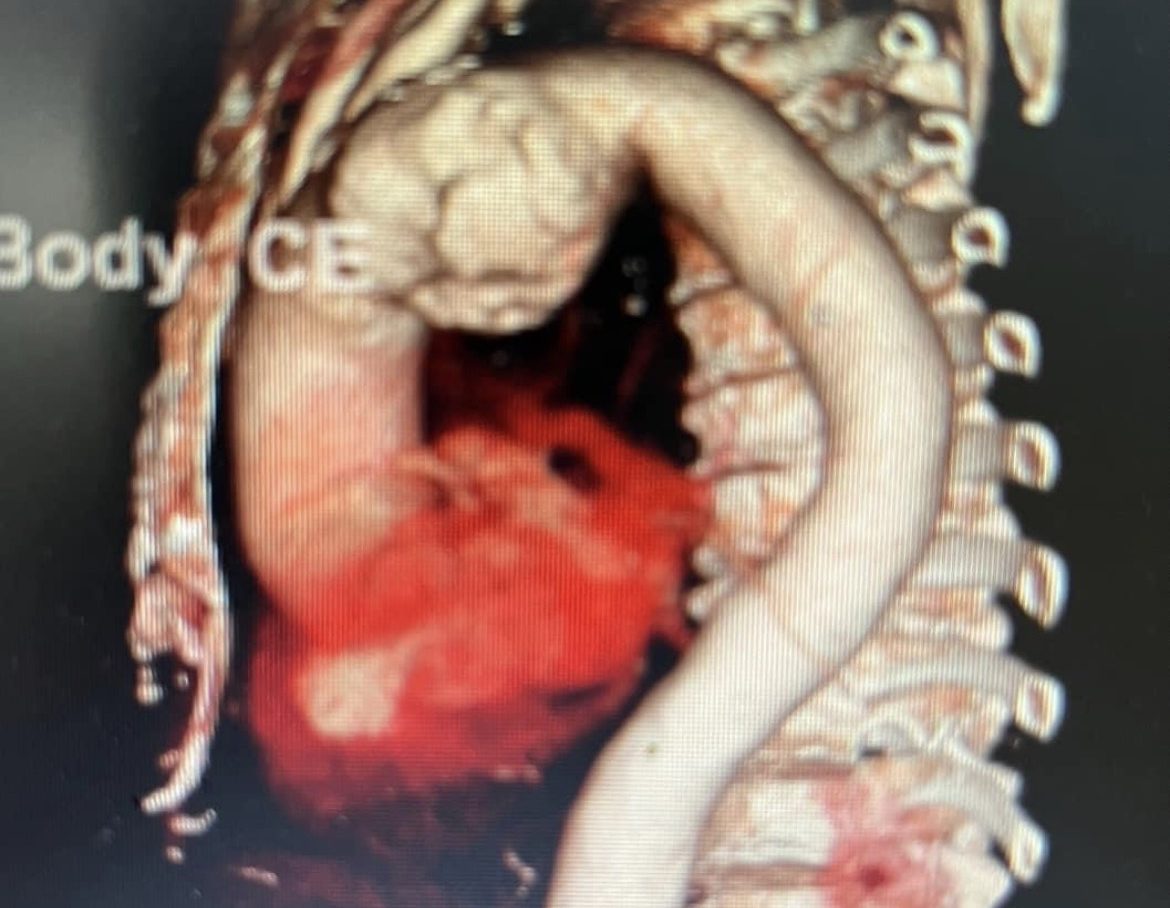

Sau khi thăm khám, làm các xét nghiệm cận lâm sàng và chụp MSCT, bệnh nhân được chẩn đoán phình lớn động mạch chủ ngực ngay dưới động mạch dưới đòn trái, kích thước 57 x 59mm, khối phình gây triệu chứng đau ngực và khàn tiếng do liệt dây thần kinh quặt ngược trái.

Hình ảnh khối phình lớn trên phim chụp CLVT